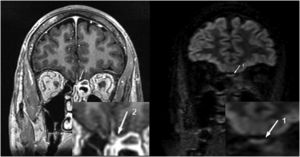

A 39-year-old man male presented to the emergency room with right periocular headache, different and more intense than his usual migraine; cough; pleuritic chest pain; anosmia and dysgeusia for three days. Auscultation revealed bibasal crackling rales with no other abnormal signs in the physical and neurological examination. His blood tests showed increased levels of D-dimer, interleukin 6, ferritin and C-reactive protein. The real-time reverse-transcriptase-polymerase-chain-reaction assay from oropharyngeal swab was positive for Severe Acute Respiratory Syndrome Coronavirus-2 (SARS-CoV-2) and serum antibody testing exhibited positive IgM and negative IgG antibodies versus SARS-CoV-2. Chest X-ray findings were described as bibasal opacities with associated interstitial pattern. The SARS-CoV-2 RT-PCR in cerebrospinal fluid (CSF) was negative and all the CSF parameters were within normal range. He was therefore diagnosed with bilateral COVID pneumonia. On the 10th day since the onset of symptoms, after a remarkable improvement of the clinic and completely recovery of the smell, a magnetic resonance imaging (MRI) was carried out. The MRI (Fig. 1) showed bilateral localized contrast enhancement in olfactory bulbs. Pathophysiology of anosmia in Covid-19 patients is yet unknown and the neurotropism of the virus is unclear.1–2 Enhancement of olfactory bulb could suggest focal neuropathy. In the present case, it was notable that image findings persisted longer in time regardless of the symptom’s remission.